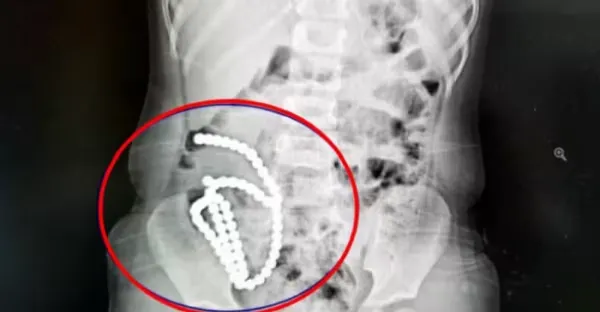

4歲妹照X光驚見「肚子整串白珠珠」媽媽證實哥哥在玩!醫嘆:一輩子毀了